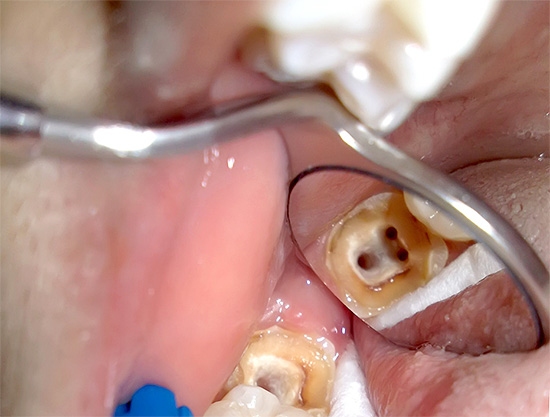

- apertura di un buon accesso alle bocche dei tre canali;

Un microscopio in endodonzia viene utilizzato, in particolare, per diagnosticare il numero di canali radicolari e la qualità del loro passaggio. Il trattamento della pulpite di un dente a tre radici al microscopio consente di trovare e trattare rapidamente anche i passaggi più difficili e ci sono molti casi simili nella pratica di un dentista.

Un microscopio endodontico ci consente di dire con quasi il 100% di certezza alla fine del trattamento che tutti i canali sono stati passati e correttamente sigillati. È lui che ti consente di controllare ogni fase del trattamento della pulite, prevenendo ulteriori complicazioni. Il trattamento tradizionale senza l'uso di un microscopio è spesso associato alla presenza di conseguenze negative a lungo termine, ad esempio a causa del fatto che il medico semplicemente non ha potuto vedere il canale aggiuntivo nel dente e lo ha perso durante il trattamento, lasciando una polpa infetta al suo interno.

A volte, durante il trattamento della pulpite, il medico trova 3 canali, ma in realtà c'è un quarto canale (o addirittura un quinto) "ben nascosto" nel dente. Ci sono casi in cui non manca un canale, ma diversi, poiché ci sono opzioni complesse per la loro posizione nel dente.